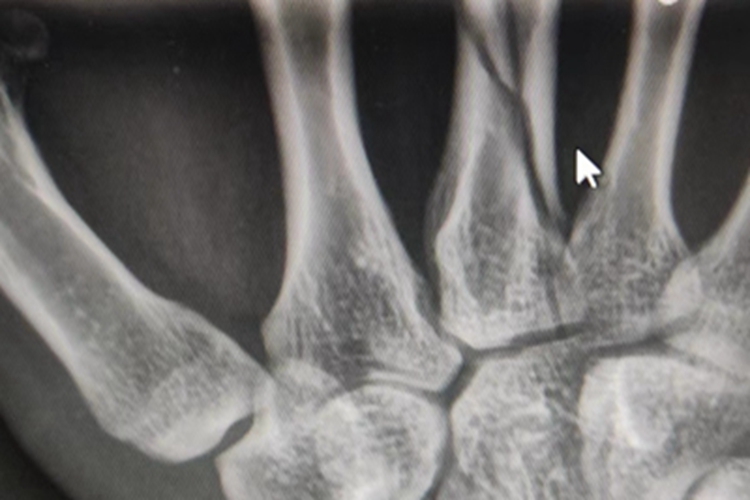

骨折可发生在部分患者的手掌,有时表现为局部骨头的中部有裂纹,形状不规则,没有明显的错位,伴有一定的疼痛感。患者正常工作、生活因此受影响。

骨折手掌的骨头有裂纹,是骨组织受暴力作用而发生。常见原因有人身攻击、运动伤、摔伤、道路交通事故伤、工伤等。骨质疏松症会增加此种情况发生的可能性。

对于骨折手掌的骨头有裂纹情况,需要根据具体情况,采取合适的治疗措施,常见的有内固定手术、外固定手术等。同时患者可应用药物,如对乙酰氨基酚片、布洛芬片等,可以缓解疼痛,必要时应用盐酸氢吗啡酮注射液等药物。注意上述治疗均需遵医嘱进行。